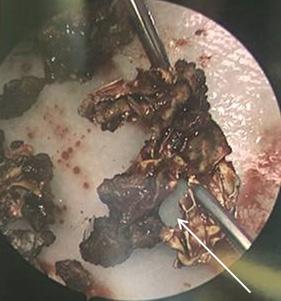

Randy Young, MD

California ACEP

American College of Emergency Physicians

Mark I. Langdorf, MD, MHPE

UC Irvine Health School of Medicine

Jorge Fernandez, MD